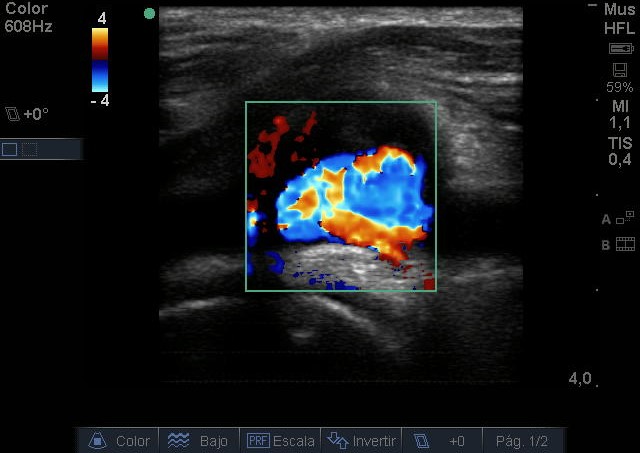

Se visualiza aneurisma de 2 centímetros con imagen compatible con trombo intramural. En modo Doppler flujo turbulento. Realizamos ecografía de rodilla contralateral y aórtica sin hallazgos reseñables.

Juicio Clínico: Aneurisma poplíteo con trombo intramural.